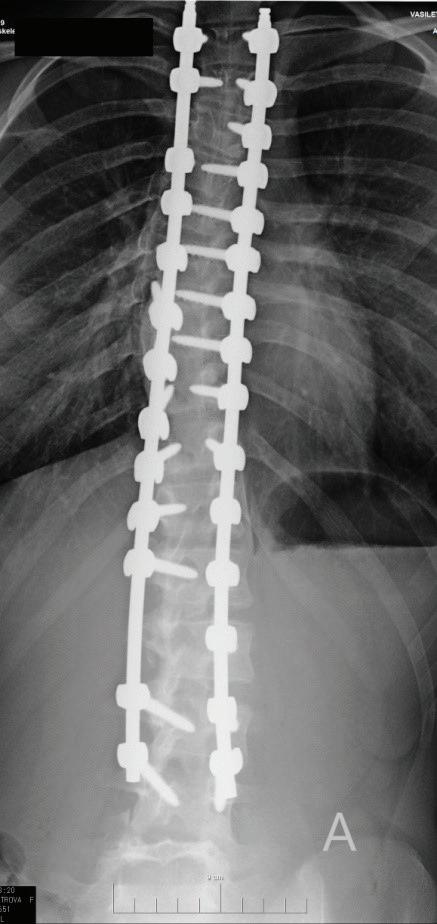

32 ПРОТОКОЛ ЗА ВЕРИФИКАЦИЯ

НА ПОЗИЦИЯТА НА ПЕДИКУЛАРНИ

ВИНТОВЕ ПРИ FREE HAND ТЕХНИКА

ЗА ОПЕРАТИВНО ЛЕЧЕНИЕ НА

ИДИОПАТИЧНА СКОЛИОЗА В ДЕТСКА

ВЪЗРАСТ

А. Иванов